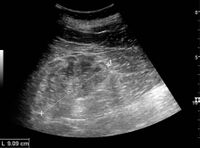

Kidney ultrasonography is useful for diagnostic and prognostic purposes in chronic kidney disease. Whether the underlying pathologic change is glomerular sclerosis, tubular atrophy, interstitial fibrosis, or inflammation, the result is often increased echogenicity of the cortex. The echogenicity of the kidney should be related to the echogenicity of either the liver or the spleen (Figure 22 and Figure 23). Moreover, decreased kidney size and cortical thinning are also often seen and especially when disease progresses (Figure 24 and Figure 25). However, kidney size correlates to height, and short persons tend to have small kidneys; thus, kidney size as the only parameter is not reliable.[54]

Chronic renal disease caused by glomerulonephritis with increased echogenicity and reduced cortical thickness. Measurement of kidney length on the US image is illustrated by '+' and a dashed line.[54]